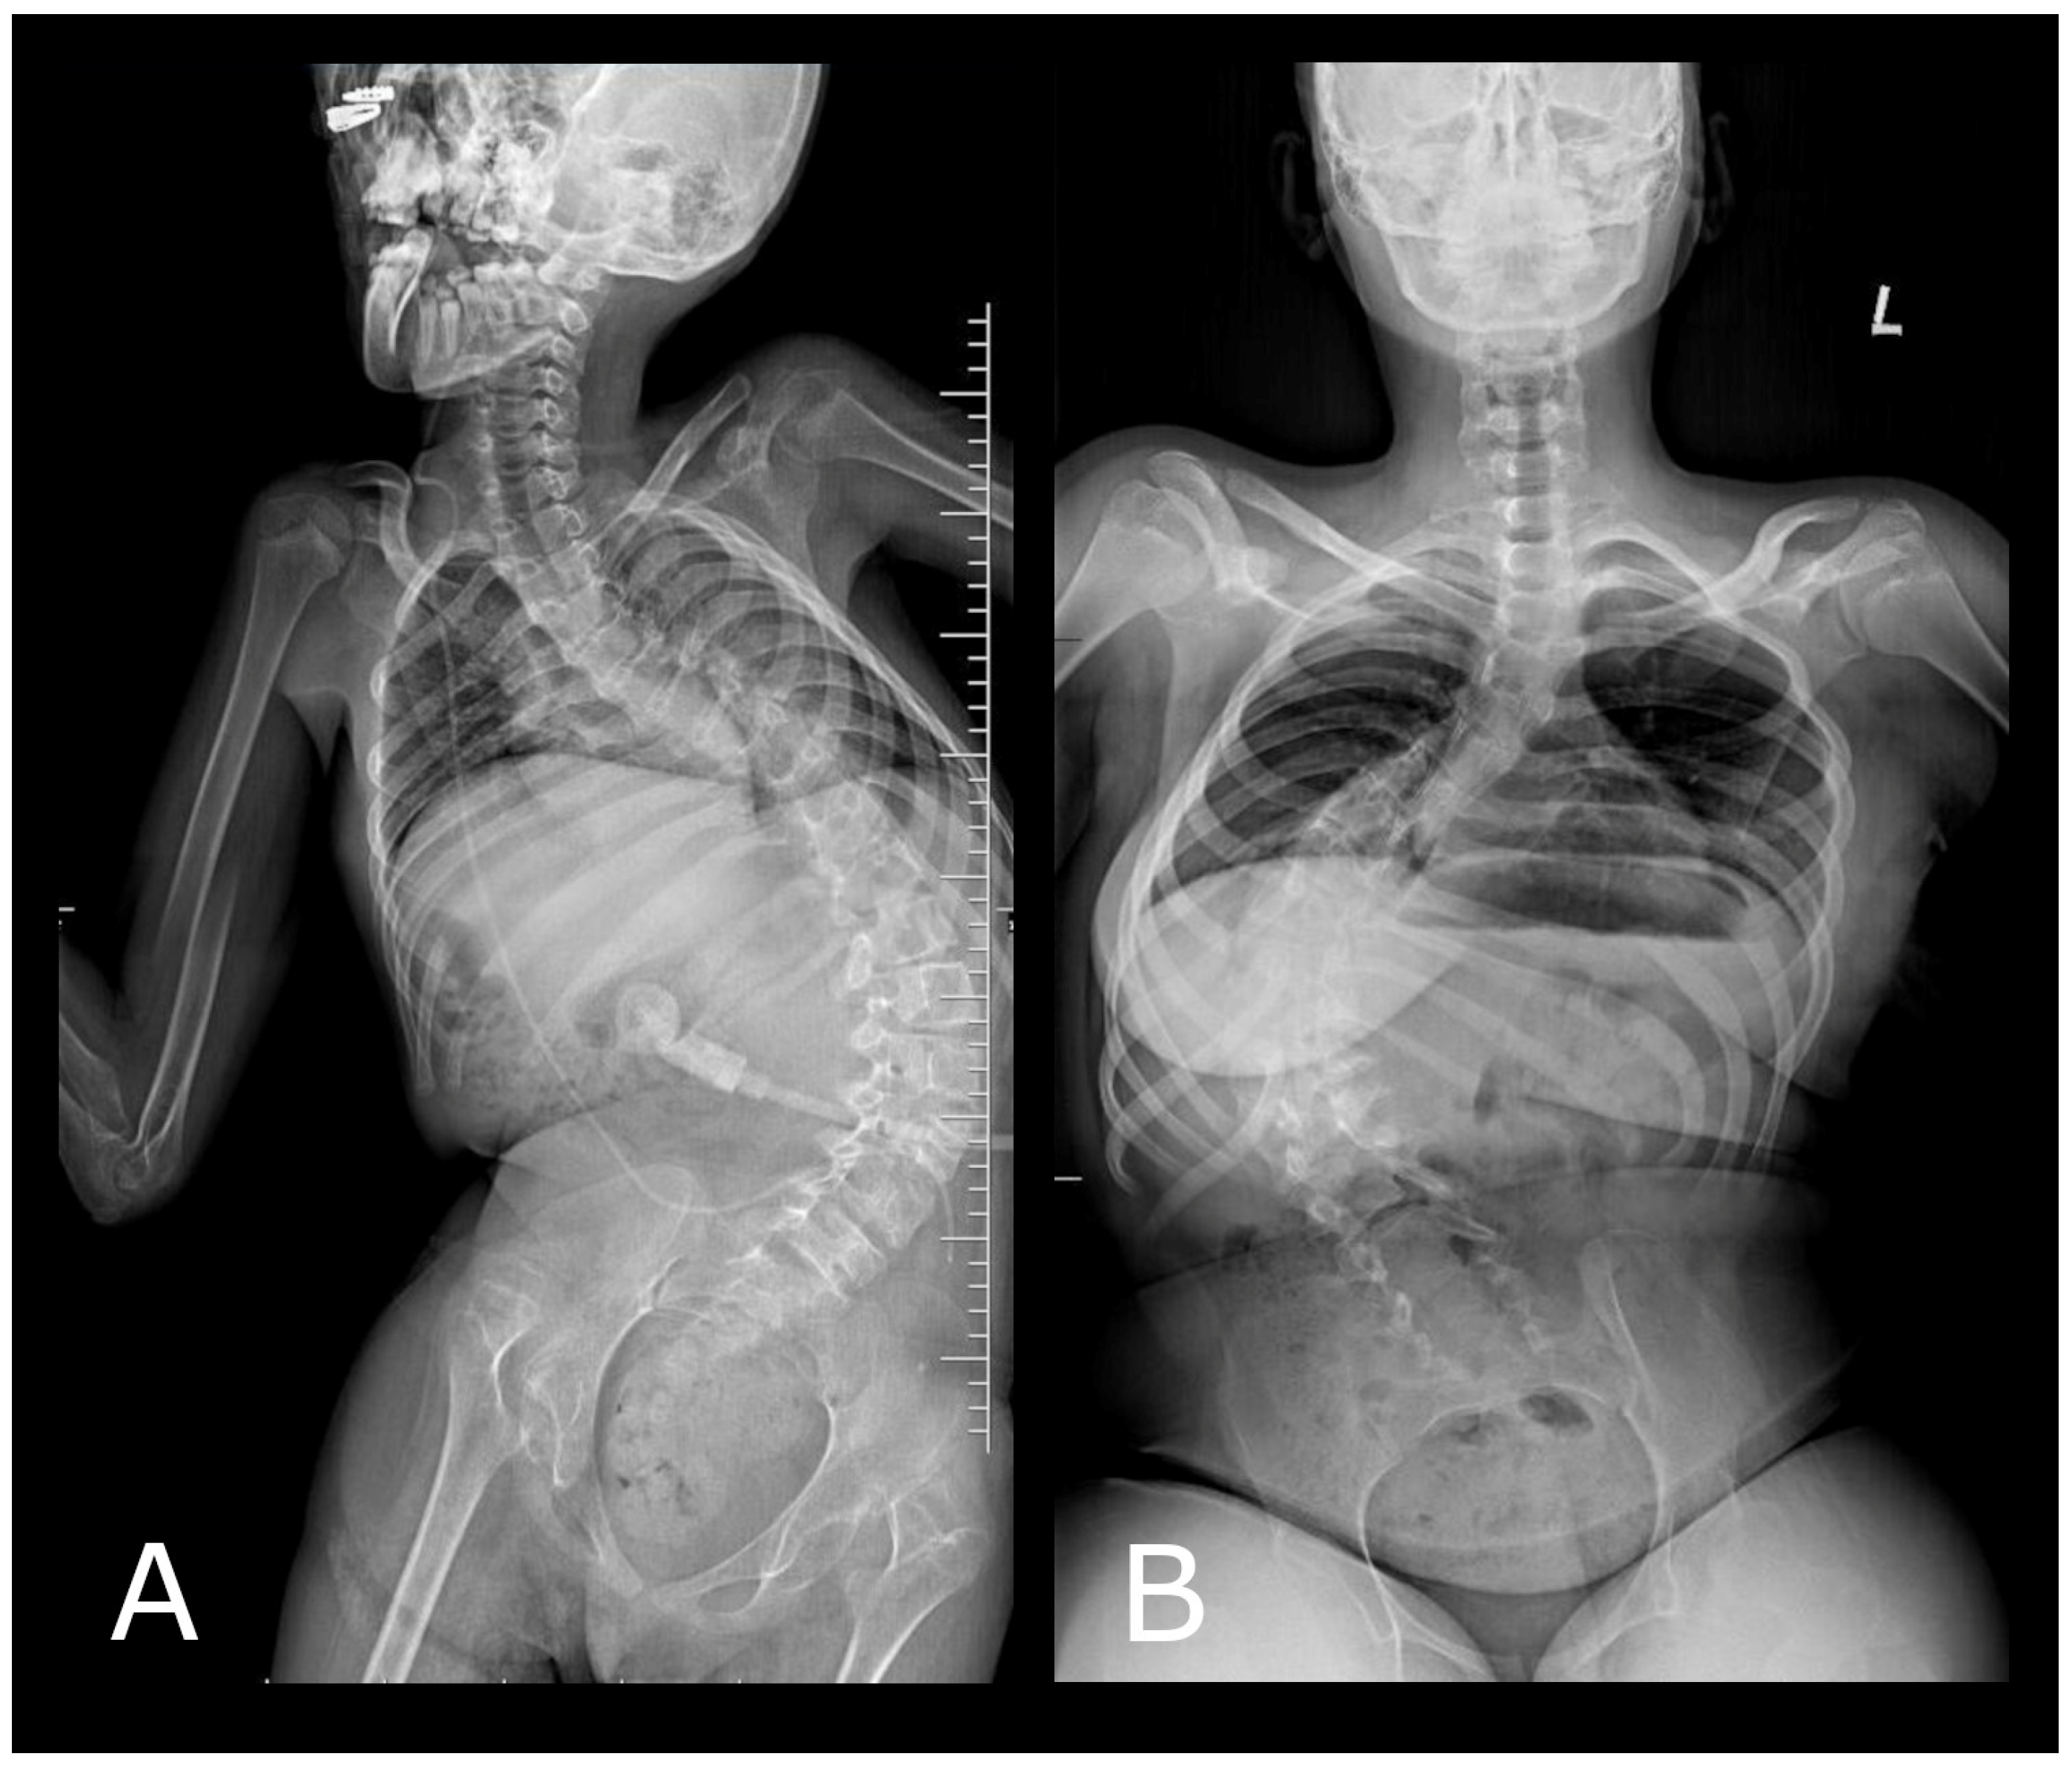

On the other hand, the AI model ChatGPT exhibited partial success in its analytic attempts. The algorithm was able to attempt an evaluation of Cobb angles in 43.5% of the images (n = 10) (Figure 4). While this did not represent a full detection rate, it did indicate that ChatGPT’s algorithm was equipped with the fundamental capacity to recognize and quantify the Cobb angle, a pivotal metric in the diagnosis of scoliosis, in almost half of the radiographic images provided. This partial detection rate by the ChatGPT model presented an opportunity for further refinement. Enhancing the algorithm’s training with a more comprehensive set of radiographic images that cover the full spectrum of scoliosis presentations could improve its detection capabilities. Additionally, the development process should incorporate advanced image processing techniques and possibly integrate machine learning methodologies that specialize in medical image analysis to increase the sensitivity and specificity of the model.

Figure 4. The above illustrates three different methods by which the ChatGPT 4 system analyzed the Cobb angle. In case (A), the ChatGPT algorithm, using color markings (green), incorrectly identified the upper and lower endplates of the vertebral bodies within the spine, which are crucial for measuring the Cobb angle. However, in examples (B,C), ChatGPT used auxiliary lines to facilitate the calculation of the Cobb angle value.